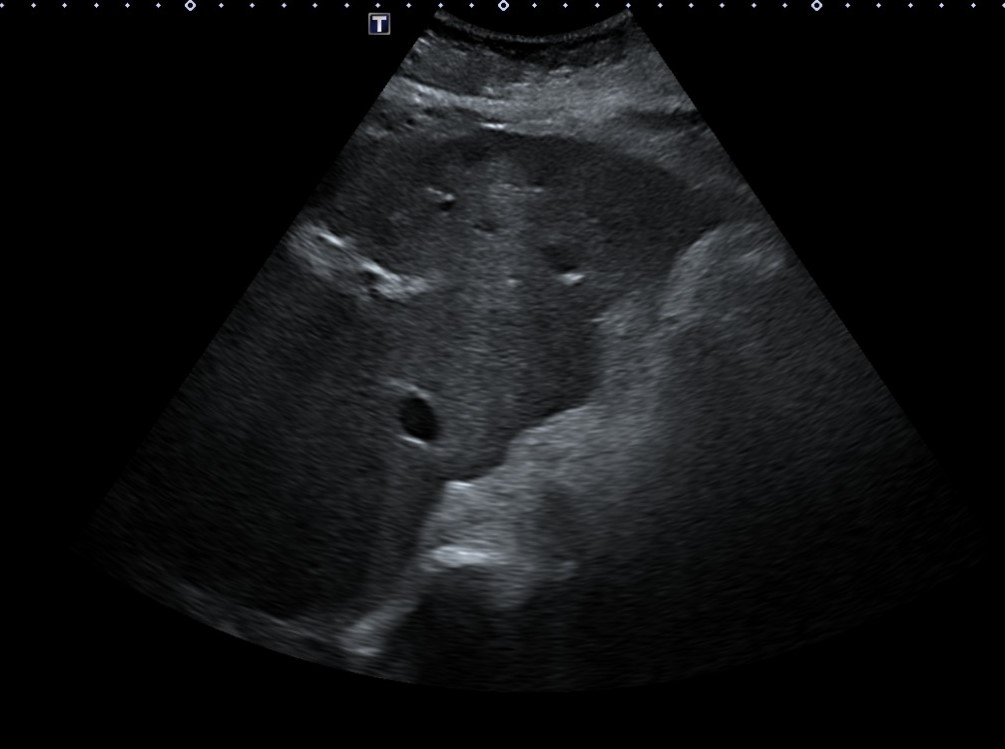

Ante resultados analíticos se realiza ecografía clínica a pie de cama. Se evidencia parénquima hepático de consistencia irregular con lesiones hipoecoicas sugestivas de metástasis tumorales. Se solicita estudio reglado.

En TC abdominal-pélvico informan:

Múltiples lesiones hipodensas hepáticas en probable relación con metástasis sin poder descartar sobreinfección de las mismas dado los datos clínicos aportados. Adenopatías retroperitoneales patológicas.